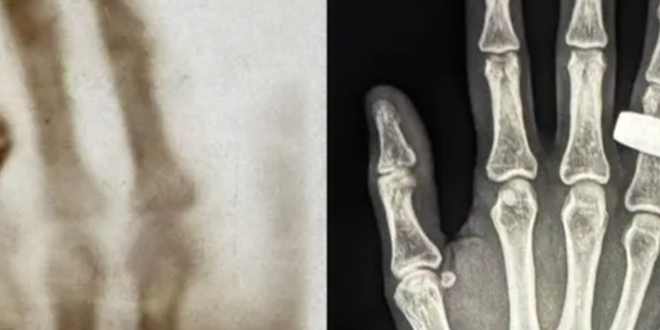

كُتب فصل جديد في تاريخ الأشعة السينية على ارتفاع مئات الأميال فوق كوكب الأرض، حيث تم التقاط صورة أشعة سينية طبية ليد بشرية بنجاح في الفضاء لأول مرة.

وتم التقاط صور بالأشعة السينية في الفضاء تماماً مثل أول صورة بالأشعة السينية من قبل 130 عاماً، حيث تُظهر هذه الصورة بالأبيض والأسود يداً بها خاتم، على غرار الصورة في عام 1895، حين اكتشف الفيزيائي الألماني فيلهلم رونتغن الأشعة السينية بالصدفة أثناء تجربته على أشعة الكاثود، و أدرك إمكانياتها الطبية، فالتقط أول صورة بالأشعة السينية ليد زوجته وهي ترتدي خاتماً.

وأحدثت هذه الصورة ثورةً في التصوير الطبي إلى الأبد، وأعاد طاقم فرام 2 إنشاء تلك الصورة بالأشعة السينية في ظل انعدام الجاذبية على ارتفاع حوالي 200 ميل فوق سطح الأرض، إذ التُقطت الصورة داخل كبسولة فضائية تتسع لأربعة أشخاص وتسافر بسرعة 17.500 ميل في الساعة.

واستخدمت التجربة نظام أشعة سينية محمولاً مُعدّلاً لرحلات الفضاء، وكانت هناك مخاوف في البداية من أن زيادة الإشعاع الخلفي قد تُؤثر سلباً على جودة الصورة.

وقال لوني بيترسن، الباحث المشارك في مشروع سبيس إكس راي، والأستاذ المشارك في قسم علوم الطيران والفضاء بمعهد ماساتشوستس للتكنولوجيا: “فيما يتعلق بالأساليب، كان أحد مخاوفي هو أن زيادة الإشعاع الخلفي قد تُقلل من جودة الصورة، مما قد يؤدي إلى انخفاضها عن المعايير السريرية، ومن الصور الأولى التي تلقيناها من الفضاء، يبدو أن الجودة ممتازة، أنا متحمس جداً لمواصلة تحليل المجموعة الكاملة من الصور”.